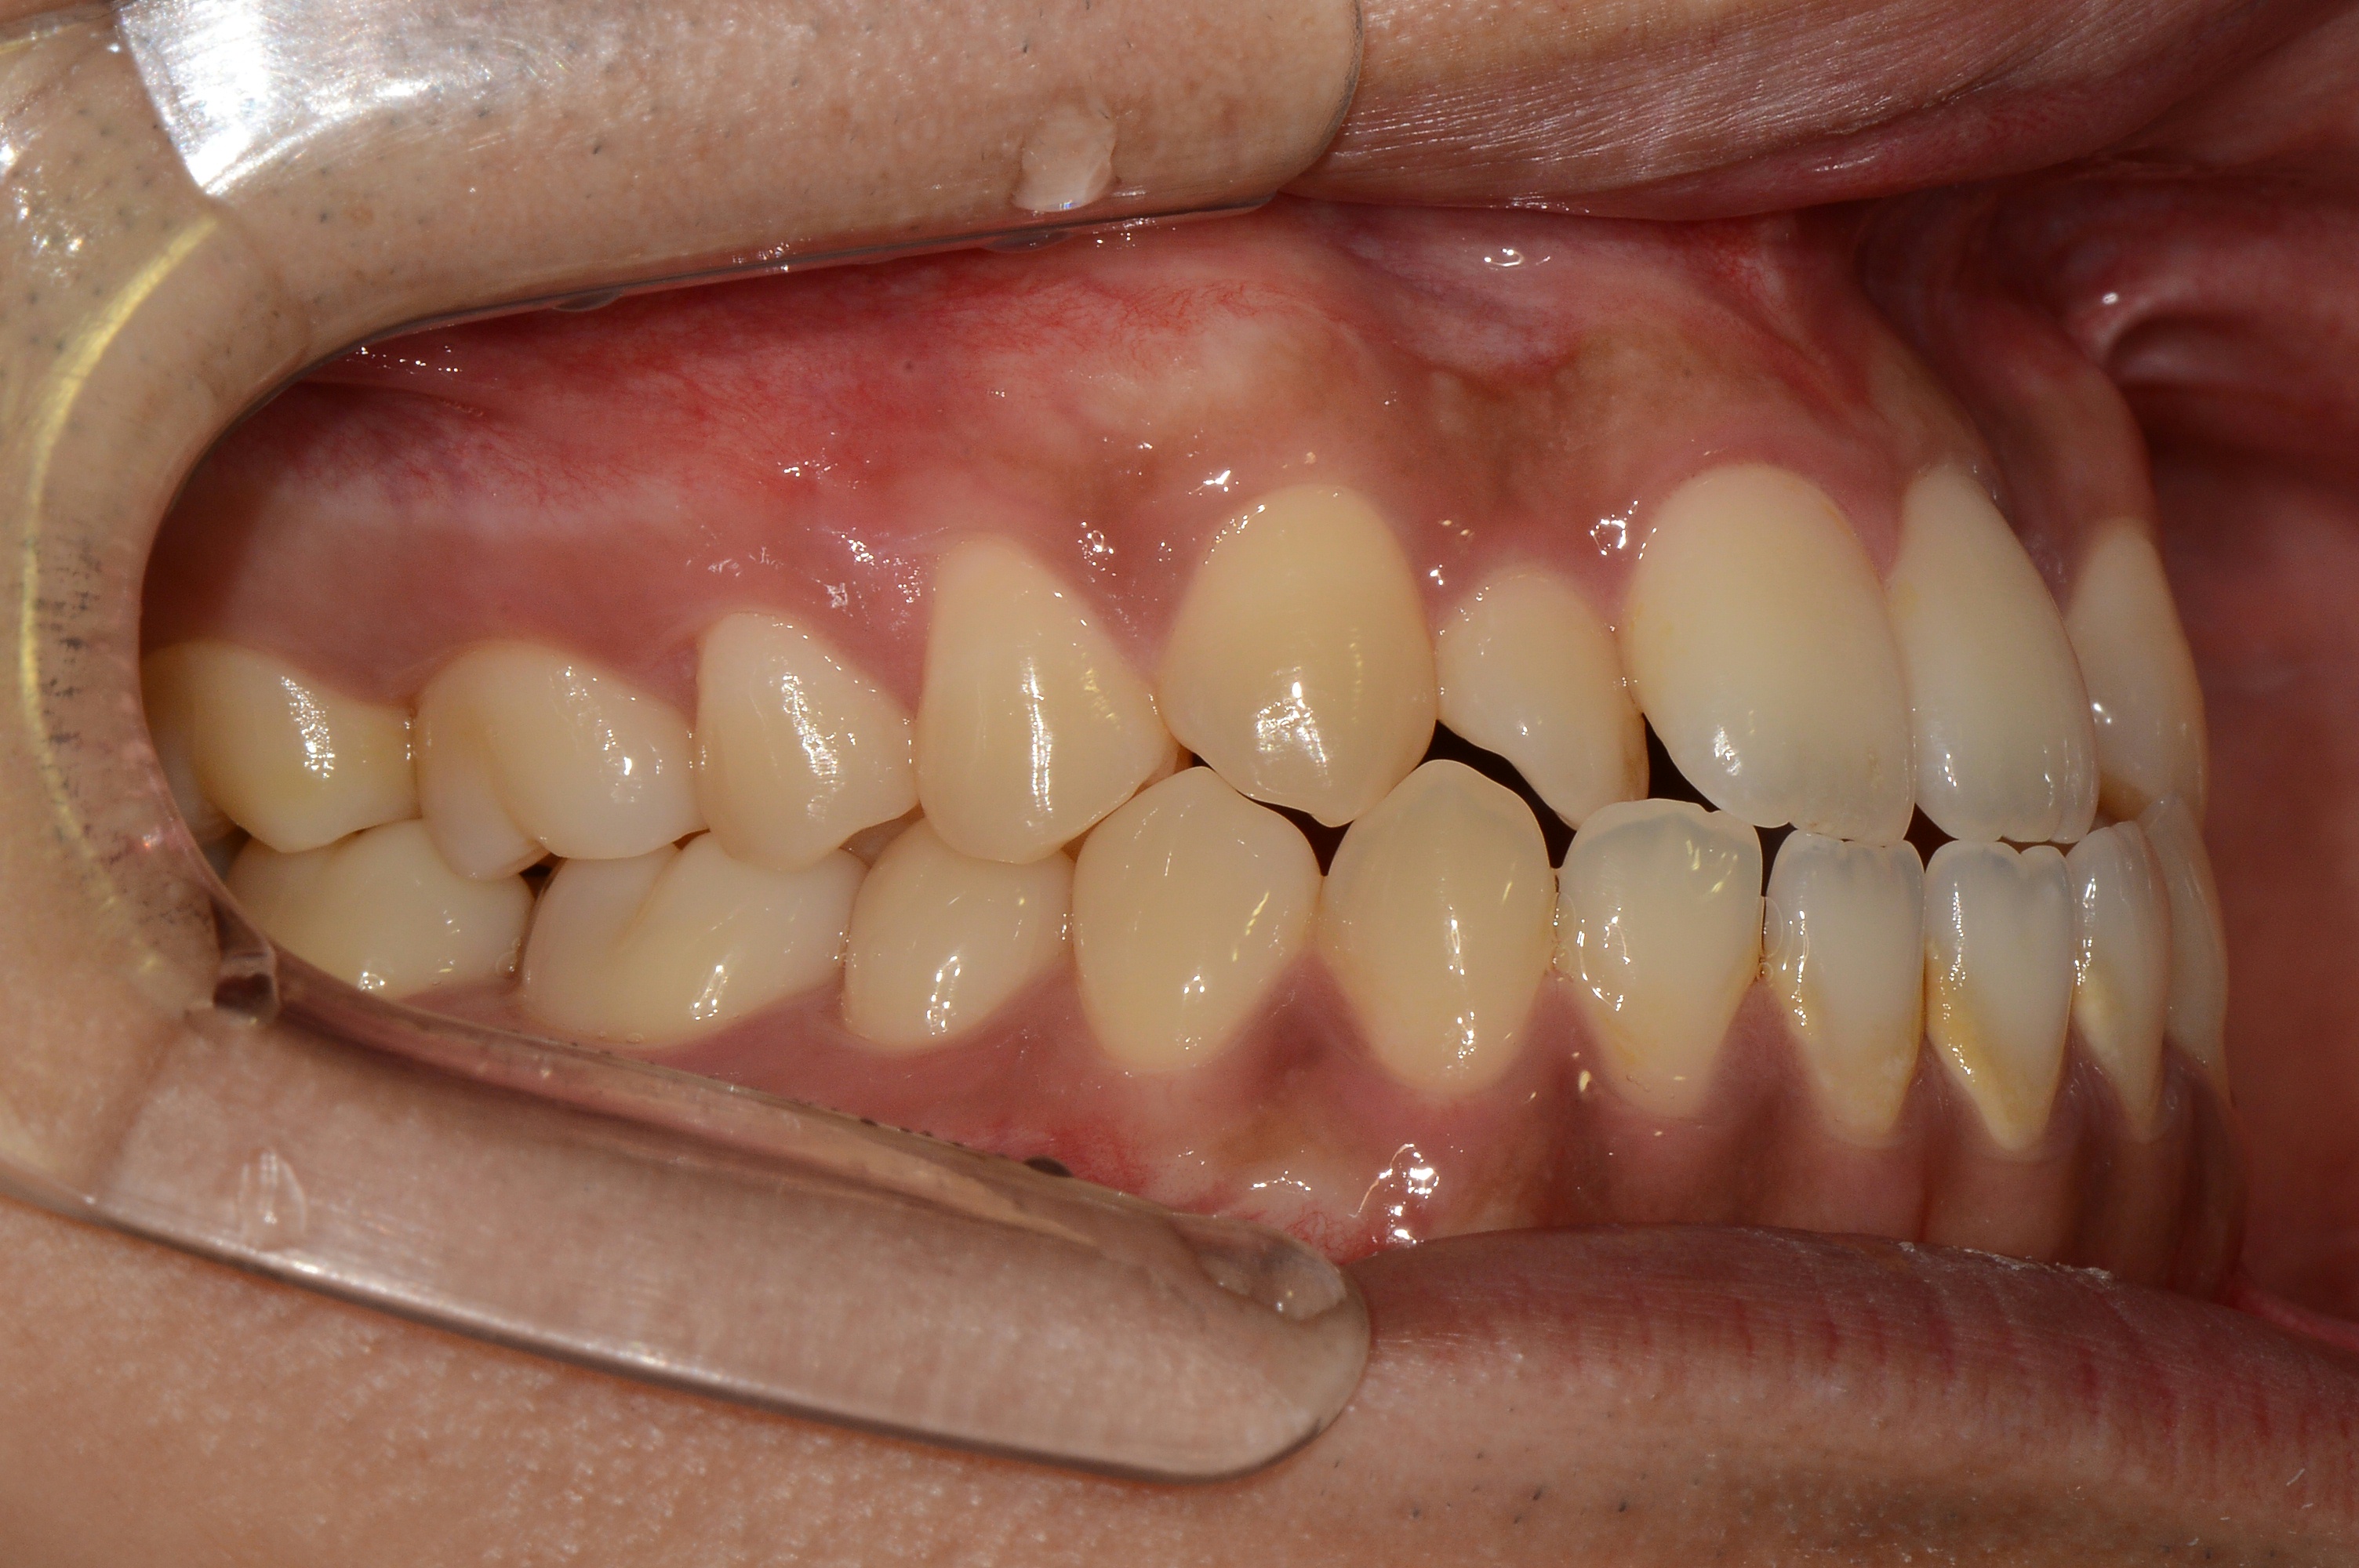

치료 후 사진입니다.